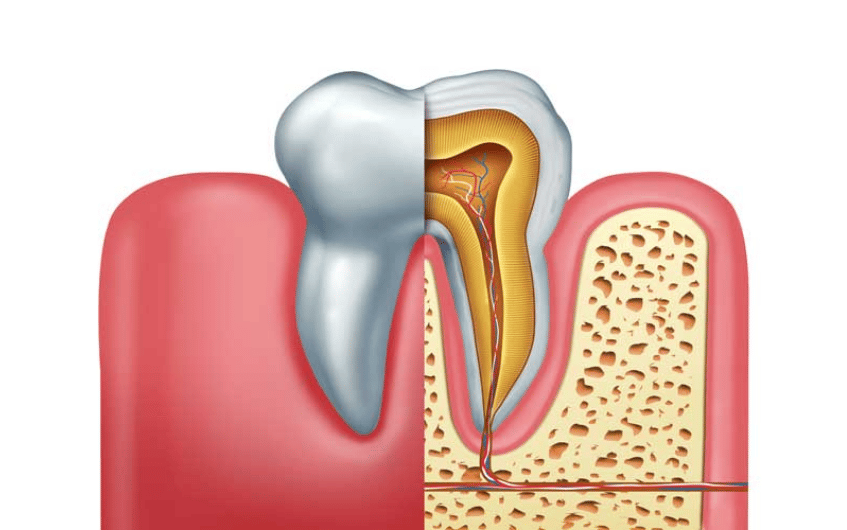

3. Strength

Dental implants are immensely strong. They’re almost as strong as your natural teeth. This is why you hardly get any added diet restrictions when you get your dental implants.

4. Preserves your facial structure

When there’s no tooth to support over your jawbone, your jawbone starts to recede, changing your facial structure and making you look older. Dental implants are implanted right into your jawbone, preventing your jawbone from receding.